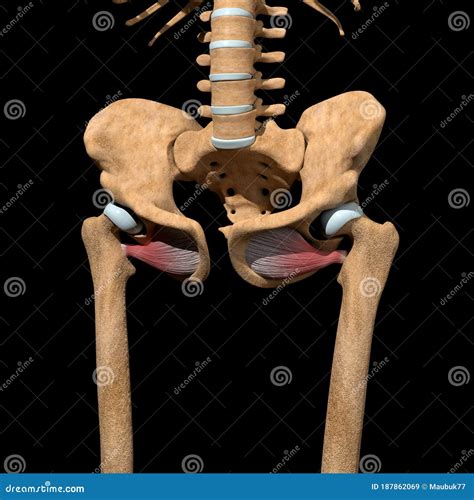

Anatomical representation of the hip region

The Obturator Externus Muscle is situated in the upper portion of the medial thigh. It is a flat, triangular muscle that originates from the external surface of the obturator membrane and the surrounding bony margins of the obturator foramen. From this origin, the fibers pass laterally, wrapping around the neck of the femur, and insert into the trochanteric fossa of the femur.

Because of its deep positioning, it is covered by several larger muscles, including the adductor magnus and the pectineus. Its proximity to the hip joint capsule makes it an intimate stabilizer, helping to keep the femoral head securely seated within the acetabulum (the hip socket). Anatomically, it belongs to the lateral rotator group of the hip, working in synergy with the piriformis, gemelli, and quadratus femoris.